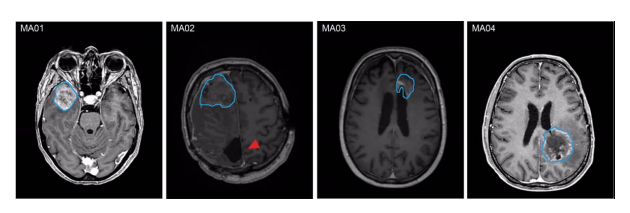

MA01-03為WHO Ⅳ級IDH野生型膠質(zhì)母細胞瘤;MA04為WHO Ⅳ級星形細胞瘤IDH突變體。

圖1 不同患者MRI